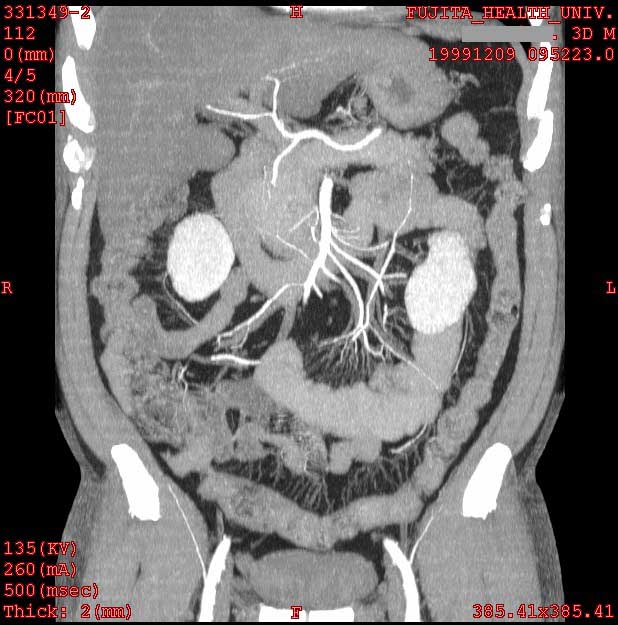

Normal colon and mesenteric arteries

2mmx4, Pitch 5, 150mAs

MIP

Data acquired by H. Anno M.D., processed by T. Takahara M.D. and K. Katada M.D.